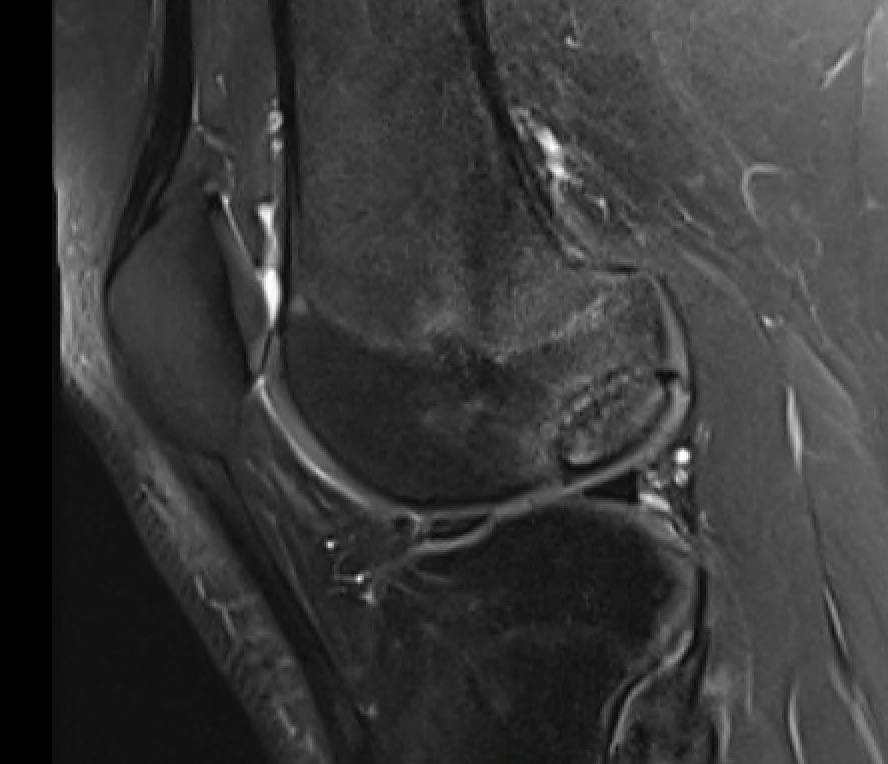

MRI Classification

Stage 1: Low signal changes, articular cartilage intact (stable)

Stage 2: Articular cartilage breached, low signal indicating fibrocartilage behind fragment (stable)

Stage 3: Articular cartilage breached, high signal indicating synovial fluid behind fragment (unstable)

Stage 4: Loose body (unstable)

Look for

- integrity of the articular cartilage

- fluid behind the lesion, suggesting instability

- displacement of the lesion

Stable

- no synovial fluid behind lesion

Unstable

- cartilage breach with synovial fluid behind lesion

Stage 1. Articular cartilage intact

Stage 2. Articular cartilage breach, but low signal intensity behind fragment

Stage 3. Articular cartilage breach and synovial fluid behind fragment (unstable)

Stage 4. Loose body

Minimally displaced loose body

Completely detached